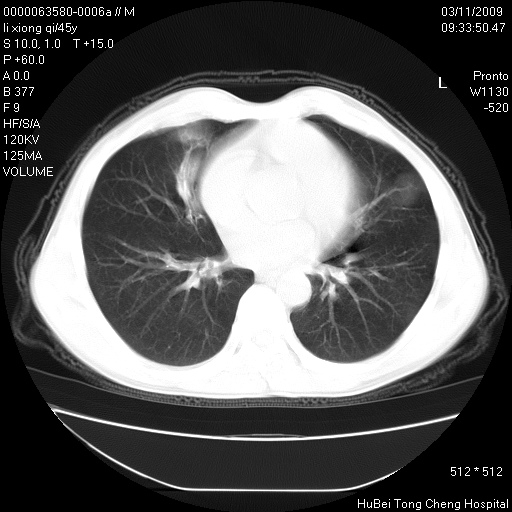

患者 男,45岁。胸痛,咳嗽伴痰中带血1月余。

临床诊断:肺结核?

胸部ct轴位平扫(层厚10mm,螺距1.5,重建间隔10mm),图像如下: